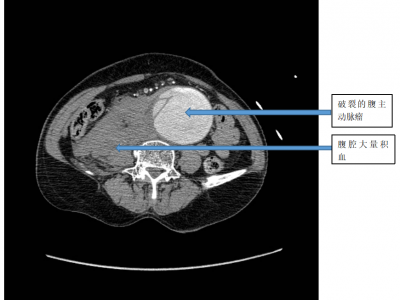

“不定时炸弹”——腹主动脉瘤